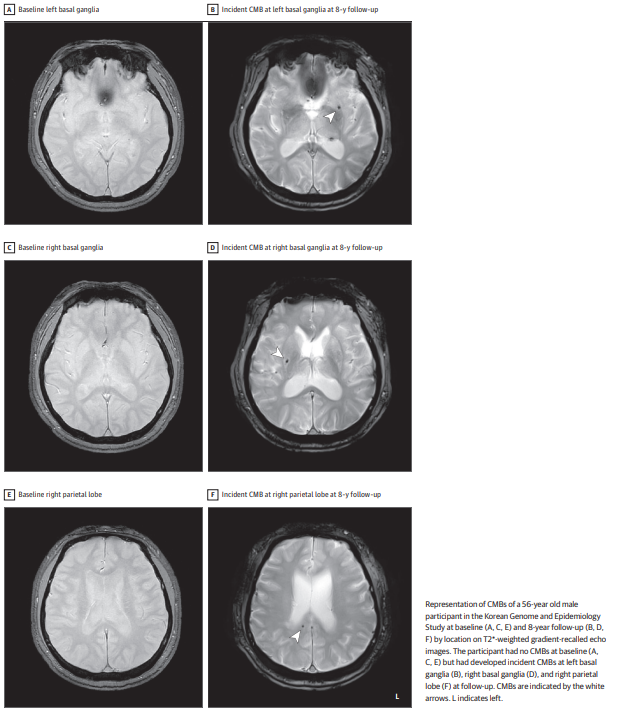

图:基线期和随访期的脑微出血图像

脑微出血是脑小血管病变的早期影像学标志,在梯度回波T2*加权磁共振成像上表现为直径小于10毫米的局灶性低信号灶。这类病变不仅是症状性卒中的前兆,还与认知功能下降和痴呆风险密切相关。在普通中老年人群中,脑微出血的患病率随年龄增长而显著上升,从中年群体的3%增至老年群体的23%。目前已知的可调控风险因素包括高血压、糖尿病、血脂异常和吸烟等,而阻塞性睡眠呼吸暂停作为一种常见的睡眠障碍,其与脑微出血的关联尚不明确。

结果显示,中重度OSA组在8年随访期间脑微出血的累积发病率为7.25%,显著高于无OSA组的3.33%。经多变量调整后,中重度OSA患者发生脑微出血的相对风险为2.14,具有统计学意义。值得注意的是,这种关联在调整APOE-ε4基因型后仍然存在,表明OSA对脑微出血的影响独立于遗传因素。此外,研究还发现大多数新发脑微出血为单发病灶,且主要位于脑叶区域。